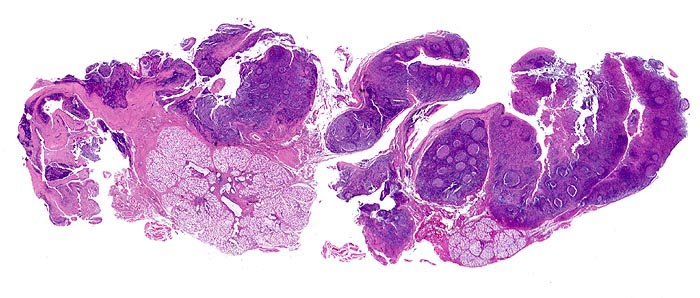

• Von nicht verhornendem Plattenepithel bedeckte Gaumentonsille.

• Follikuläre Hyperplasie:

Reaktive Keimzentren mit Zentrozyten, grösseren Zentroblasten und Kerntrümmermakrophagen. Follikel mit dunkler Mantelzone.

• Interfollikuläre Hyperplasie der T-Zone (bunte Pulpahyperplasie):

Hodgkinartige Zellen (=reaktive/aktivierte B- resp. T-Lymphozyten), kleine Lymphozyten, Immunoblasten mit zentralem Nukleolus und Plasmazellen.

• Hochendotheliale postkapilläre Venolen (gesteigerte Lymphozyten-Rezirkulation).